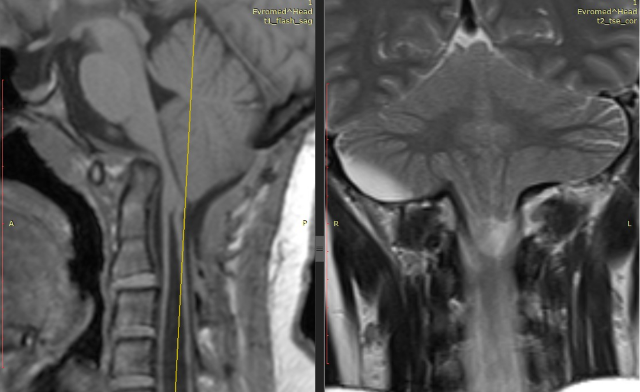

Признаки арнольда киари 1